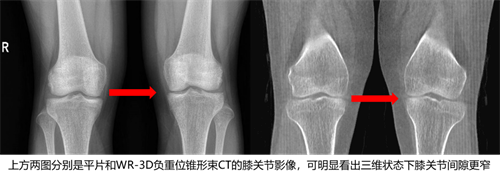

目前的动态DR不仅支持动态摄影检查,还可以实现站立位下的三维高级成像。例如安健科技最新研发的WR-3D负重位锥形束CT摄影,使用大C的Cone Beam锥束成像技术,采用平板探测器作为X线探测设备,X线和探测器环绕患者进行圆周运动实现不同角度的数据采集,并通过三维重建算法重建出患者扫描部位的三维容积图像。相对于螺旋CT具有更大的锥角及更大的Z轴覆盖范围,更低的剂量、空间分辨率更高等特点;相比静态DR,可以更精准的反应患者的真实情况,帮助医生更好的做术前规划和制定手术方案。

(图像出自安健科技)